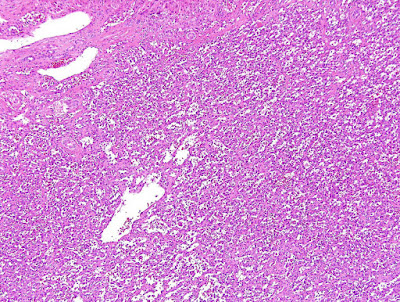

A 62 year old woman with a history of renal cell carcinoma removed years ago presented with a 2.4 cm liver mass found in CT during follow-up. A partial hepatectomy was performed.

Cut section reveals a 2.4 cm circumscribed mass with a gray-brown focally spongy appearance.

Hemangioma, anastomosing type.

Hepatic hemangioma is a common benign vascular neoplasm in both infants and adults that shares the same growth pattern and prognosis as its cutaneous counterpart. Based on its distribution, hemangioma can be classified as focal, multifocal, or diffuse. Most hepatic hemangiomas are of the cavernous type followed by the capillary type. Capillary hemangioma, including lobular capillary hemangioma (also known as pyogenic granuloma) commonly presents on the skin and mucosa, although rare liver or gastrointestinal tract examples have been reported. Capillary hemangioma is composed of a lobular proliferation of vascular channels with plump endothelial cells lining the vascular channels. Anastomosing hemangiomas in the liver, as seen in this case, are rare hepatic vascular neoplasms characterized by an interconnecting sinusoidal-like pattern of tightly packed capillary channels. The tumor appears well circumscribed grossly with a gray-brown focally spongy appearance in the liver. Low-power magnification shows a well-demarcated lesion with lobular architecture in the liver. At higher magnification the tumors consists of anastomosing sinusoidal capillary-sized vessels with scattered hobnail endothelial cells within a framework of non-endothelial supporting cells. No mitotic figures or necrosis are observed. Mild cytologic atypia is appreciated. Immunohistochemical stain for CD31 is diffusely positive.